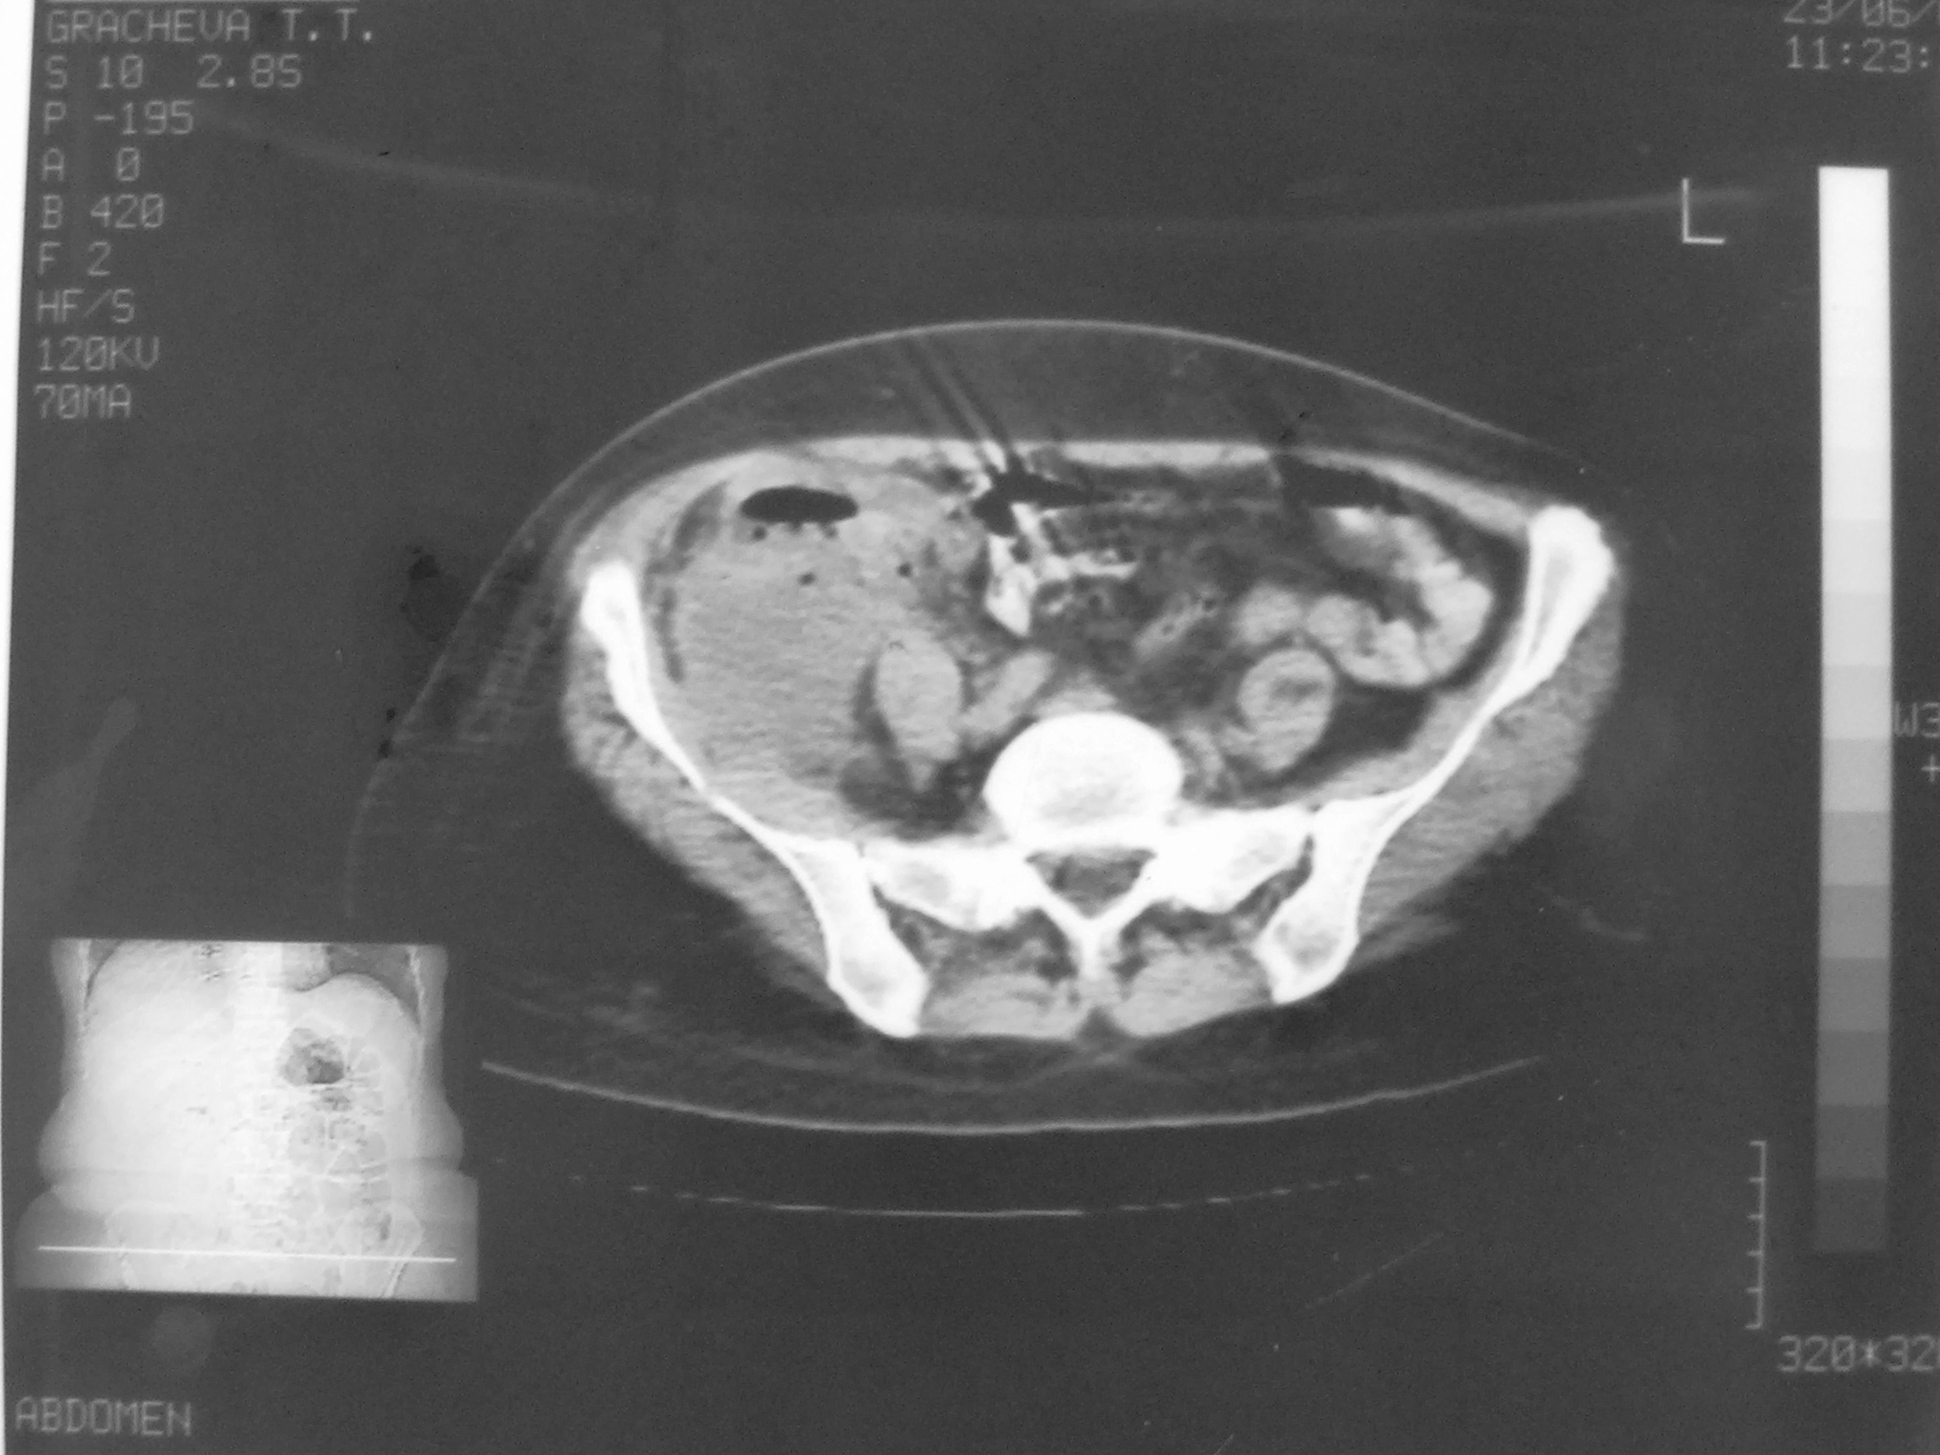

КТ-исследование абсцесса малого таза: Визуализация и диагностика

Раздел: Фотоальбом решений